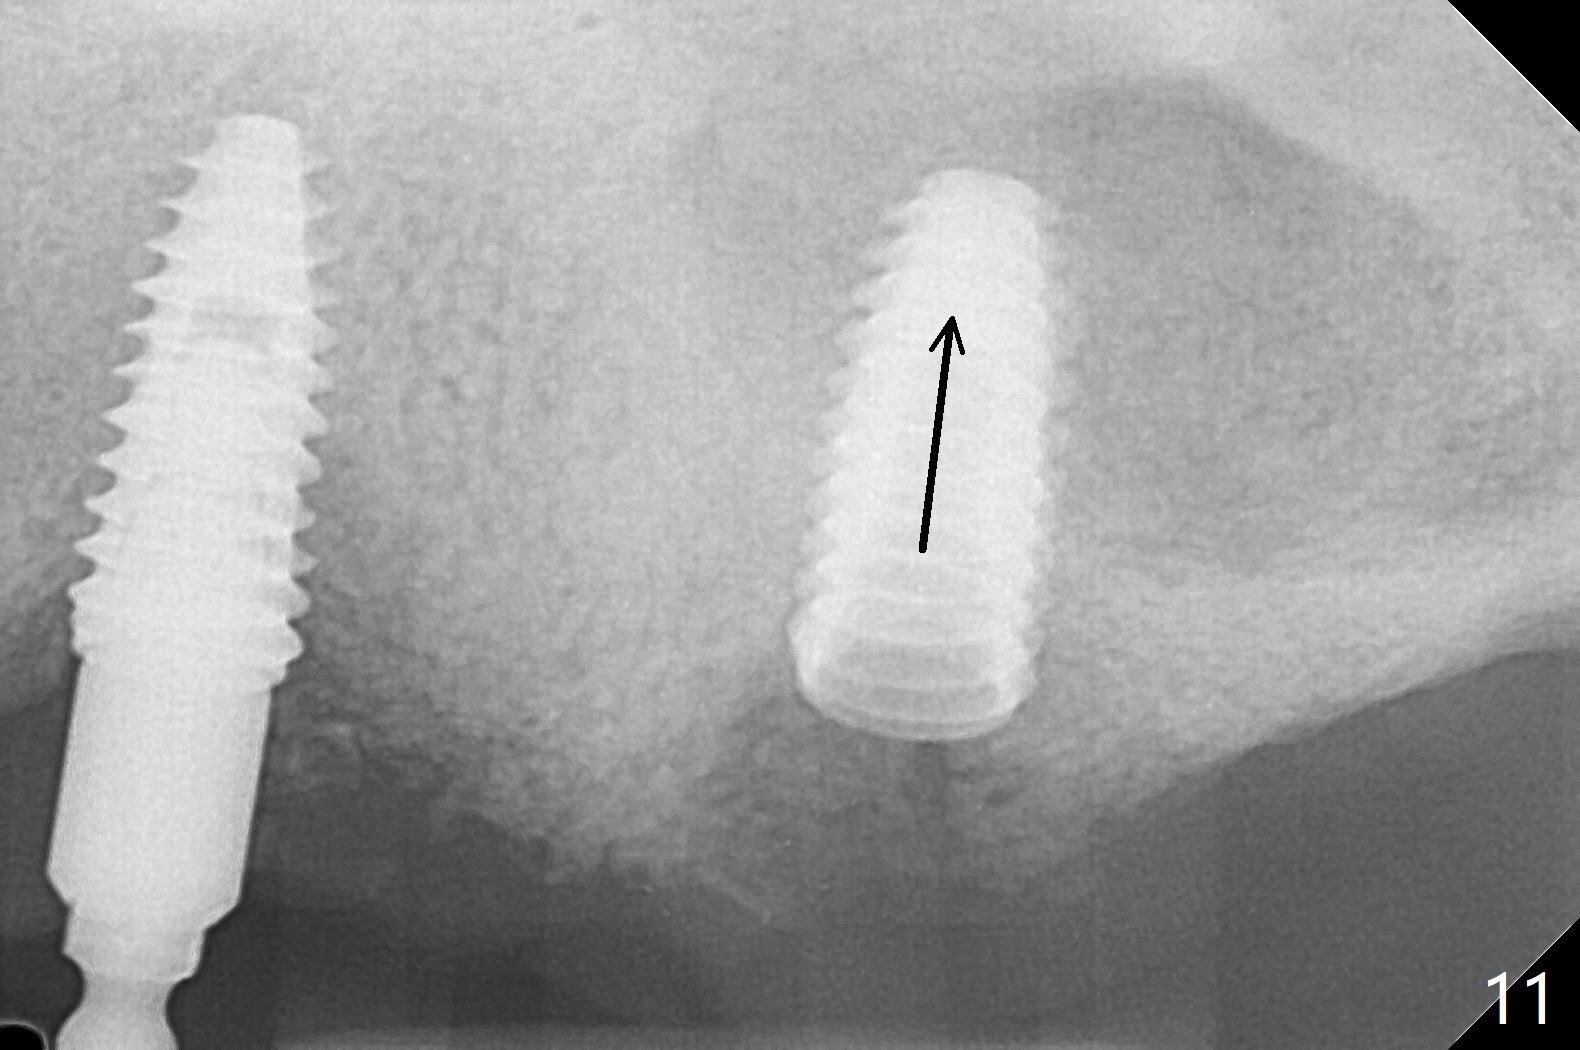

Osteotomy at #13 starts blindly (no incision or tissue punch) with bone expanders. After insertion of parallel pins, intraop CT shows that it is palatal with apparently buccal low bone density (Fig.1); the osteotomy for implant (Fig.2 green) should be shifted buccal and tilted mesial (red, parallel to #11) with incision. In contrast the position, trajectory and depth (Fig.3 <) of the initial osteotomy are acceptable at #11. The implant will be placed as it is (Fig.4). After taking a postop PA (Fig.5), the implant at #11 is placed a little deeper to make sure its slightly subcrestal placement (including distal incision at #11). Following placement of 3.5x4 and 3 mm ball abutments at #11 and 13, cortical allograft with PRF is placed around the implants, especially buccal (Fig.6,7 <). After suturing, the profile of the ball abutments is too low for RPD retention. Due to gravity other than bone density, the number of ball abutments for the maxilla should be more than for the mandible. Soft reline is done to the patient's satisfaction. The retention of the upper RPD after soft reline is satisfactory without pain 7 days postop (Fig.8). The implant at #13 is loose nearly 3 months postop (Fig.9 *: bone loss). The implant is removed while the ball abutment is untightened; the sinus floor is present. It appears that a longer and larger implant is necessary; a 4.5x10 mm dummy implant is unable to be seated deep or achieve primary stability (Fig.10). After sinus lift with 3 mm Bicon osteotome without bone graft, the dummy implant accomplishes the 2 tasks mentioned above (Fig.11). However there is no corresponding definitive implant in stock. Implant system needs to be changed; with a change in implant driver, the depth control is lost. The final implant is placed deep (Fig.12). With back up, stability is lessened; a healing screw is placed; with collagen plug, the wound is sutured (Fig.13). The wound heals 1 week postop (Fig.15). The RPD is soft relined. Retention from the ball abutment at #11 is apparently critical. The RPD and #11 implants (4 months postop) are stable, while the wound at #13 heals 1.5 months postop (Fig.15). There is space around the implant 5.5 months postop (Fig.16 *). The 5x10mm SM implant is found to be loose upon uncover and removed. After debridement, 5.3x8 mm SM and 5.5x9 mm IBS dummy implants are inserted without stability, while 6x9 mm definitive one with stability (Fig.17). Cortical allograft is placed in deficiency areas (*). The osteotomy has no roof (sinus floor), but the sinus membrane is intact. Small amount of bone graft (Fig.18 *) is placed before implantation. There appears to be bone around the new implant (Fig.19 (3D sagittal section) *).